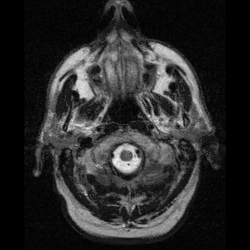

| Cerebellum and basal ganglia | |

Neuroferritinopathy is most commonly diagnosed using MRI and other neuroimaging techniques.[1] MRIs help identify the iron deposits in the cerebellum, basal ganglia, and motor cortex common to neuroferritinopathy.[8] MRIs of affected individuals also show mild cerebellar and cerebral atrophy, or tissue breakdown, and gas cavity formation in the putamen.[8] Most importantly, the MRIs show misfolded ferritin proteins and iron deposits in the glial cells of the caudate, putamen, globus pallidus, cerebral cortex, thalamus, and purkinje cells, causing neuronal death in these areas.[8]